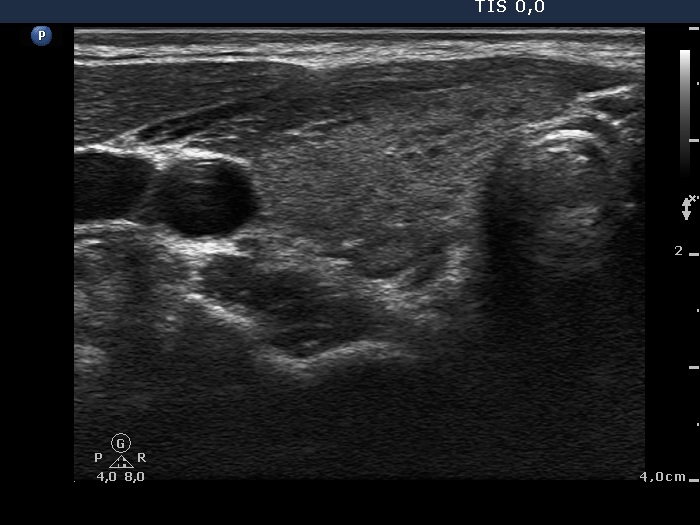

First examination (1st to third rows of images):

Clinical data: A 14-year-old boy was referred for evaluation of a nodule discovered by himself.

Palpation: a hard, not freely moveable nodule in the isthmic part of the left lobe.

Hormonal examination: indicated euthyroidism with TSH 2.09 mIU/L.

Ultrasonography revealed a hypoechogenic nodule in the ventromedial part of the left lobe. The nodule had irregular borders, contained microcalcifications and displayed perinodular and irregular intranodular blood flow.

Cytology: follicular tumor.

Based on the ultrasound and cytological pattern combined, the probability of cancer was greater than the average.